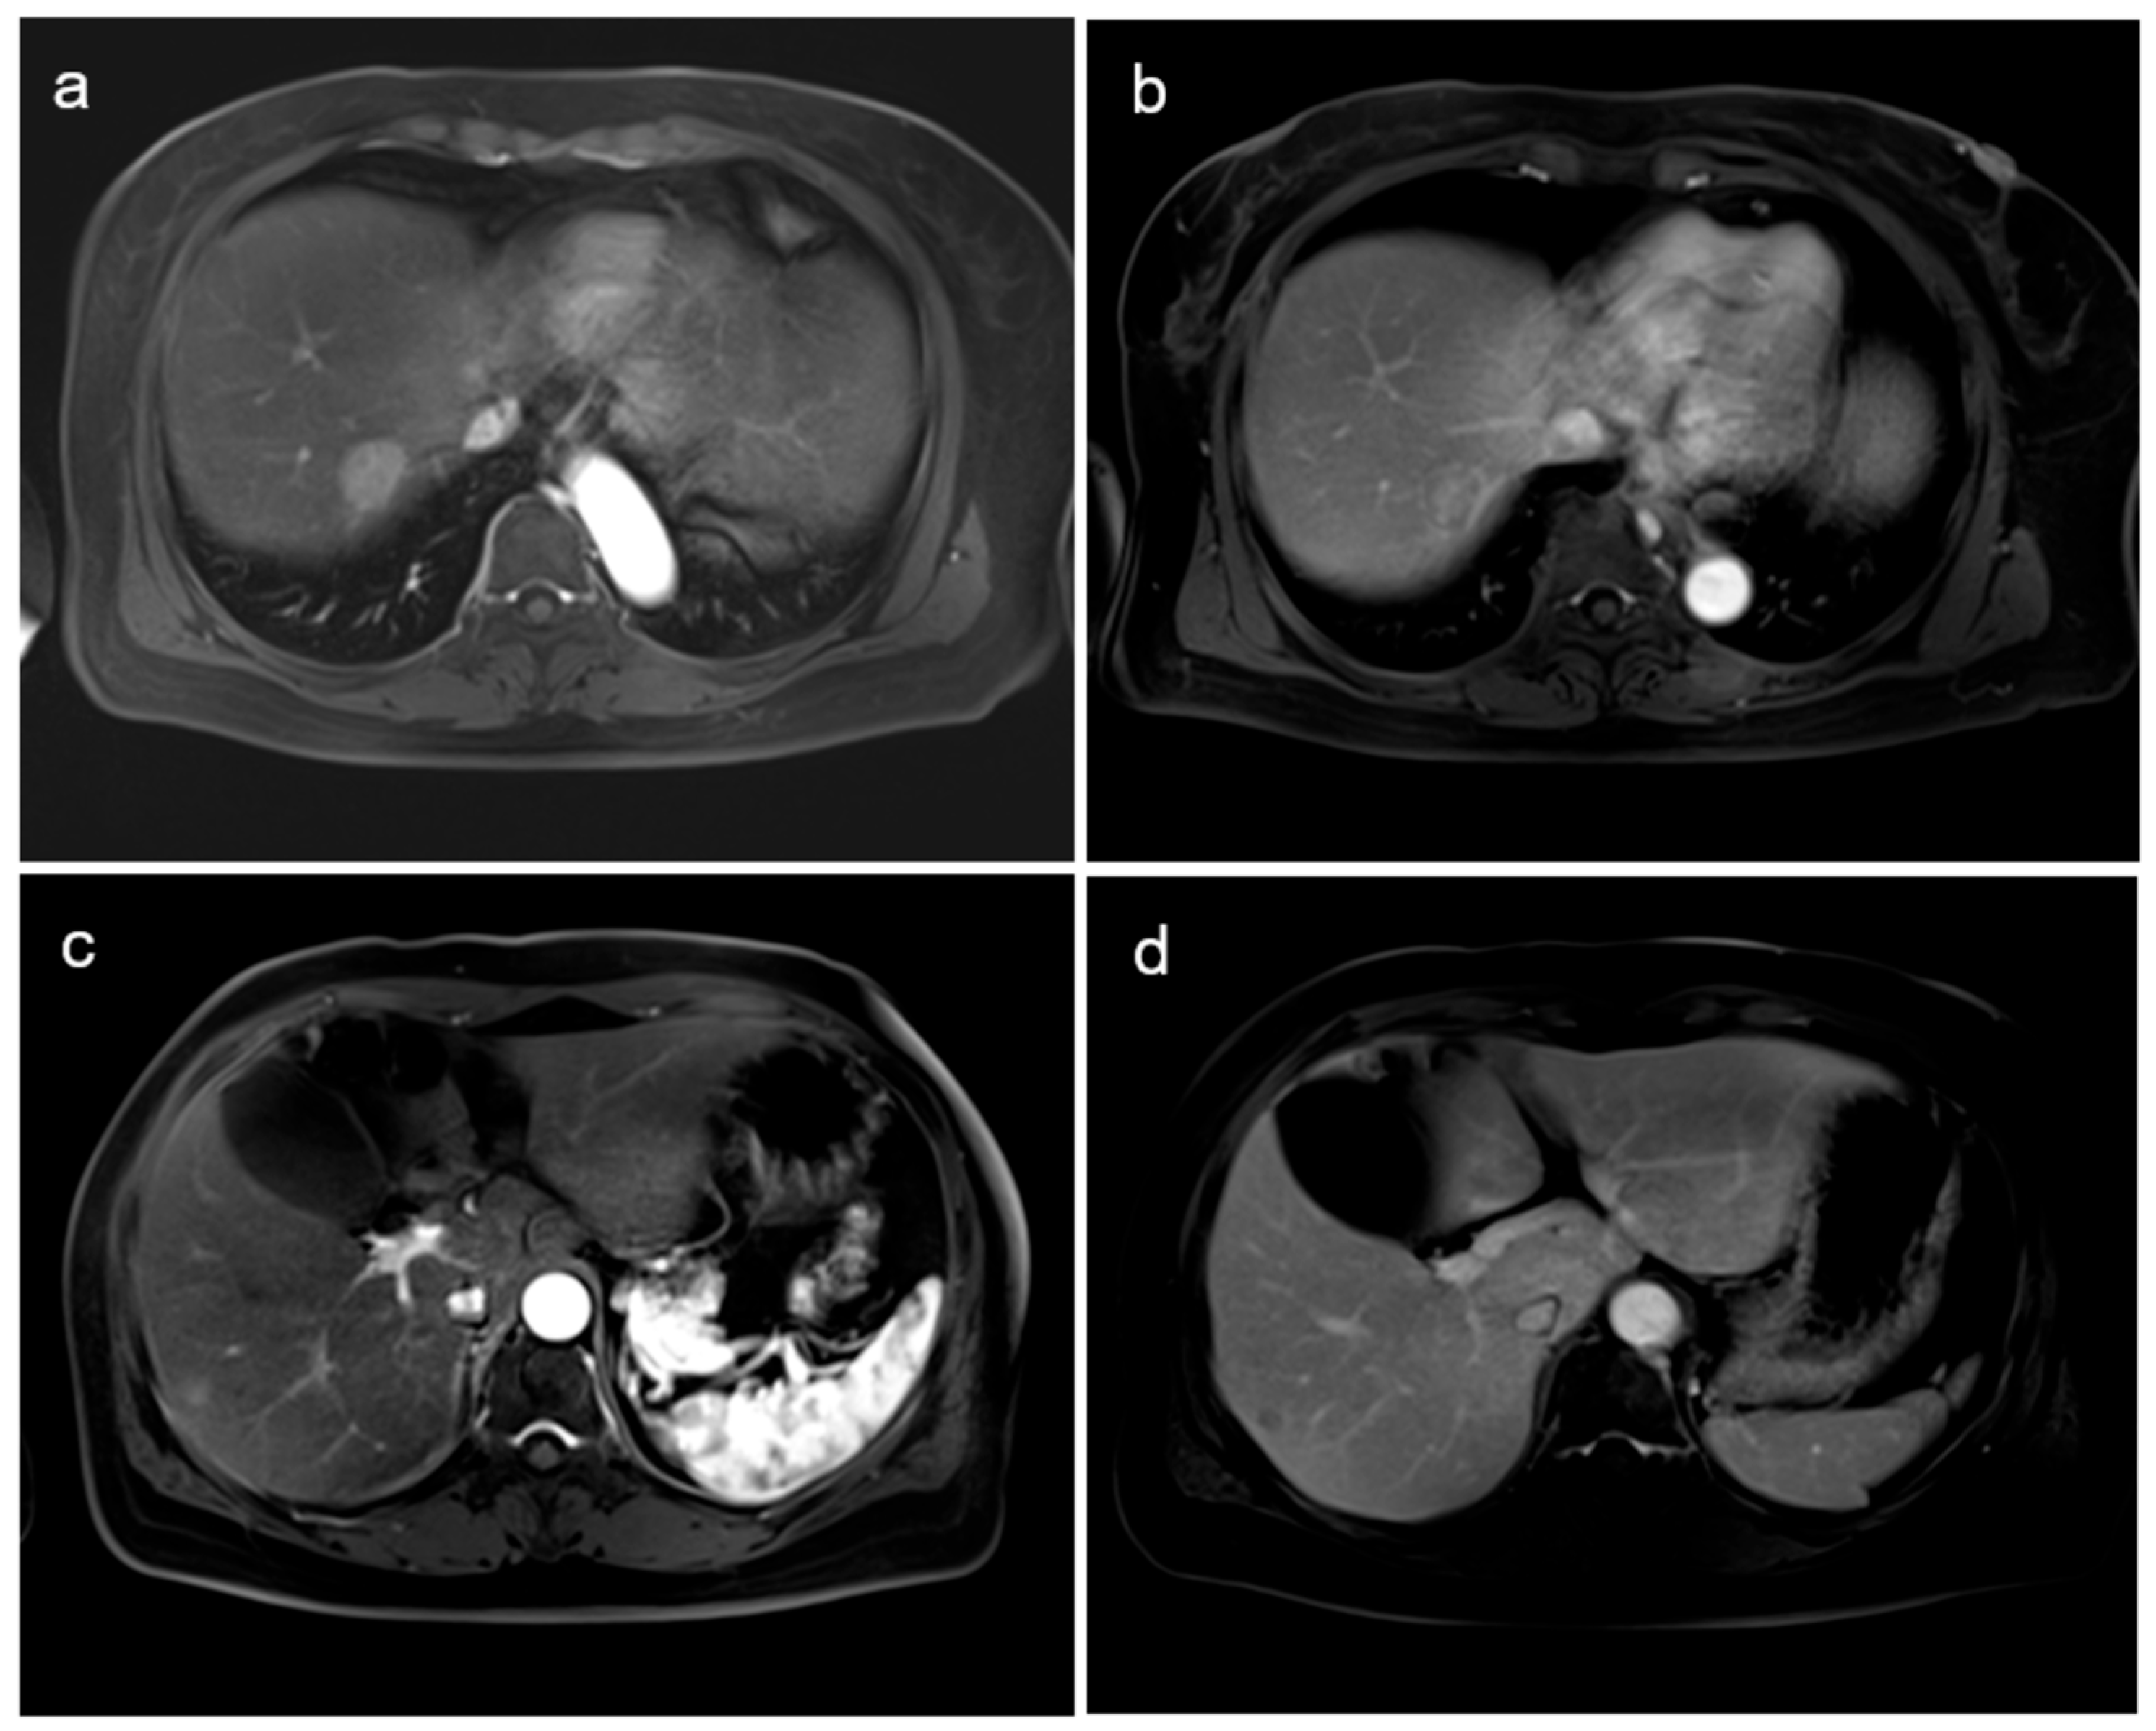

Detection of Hepatic Metastasis from Early Delayed Images of Modified Dual-Time-Point F-18 FDG PET/CT Images in a Patient with Breast Cancer